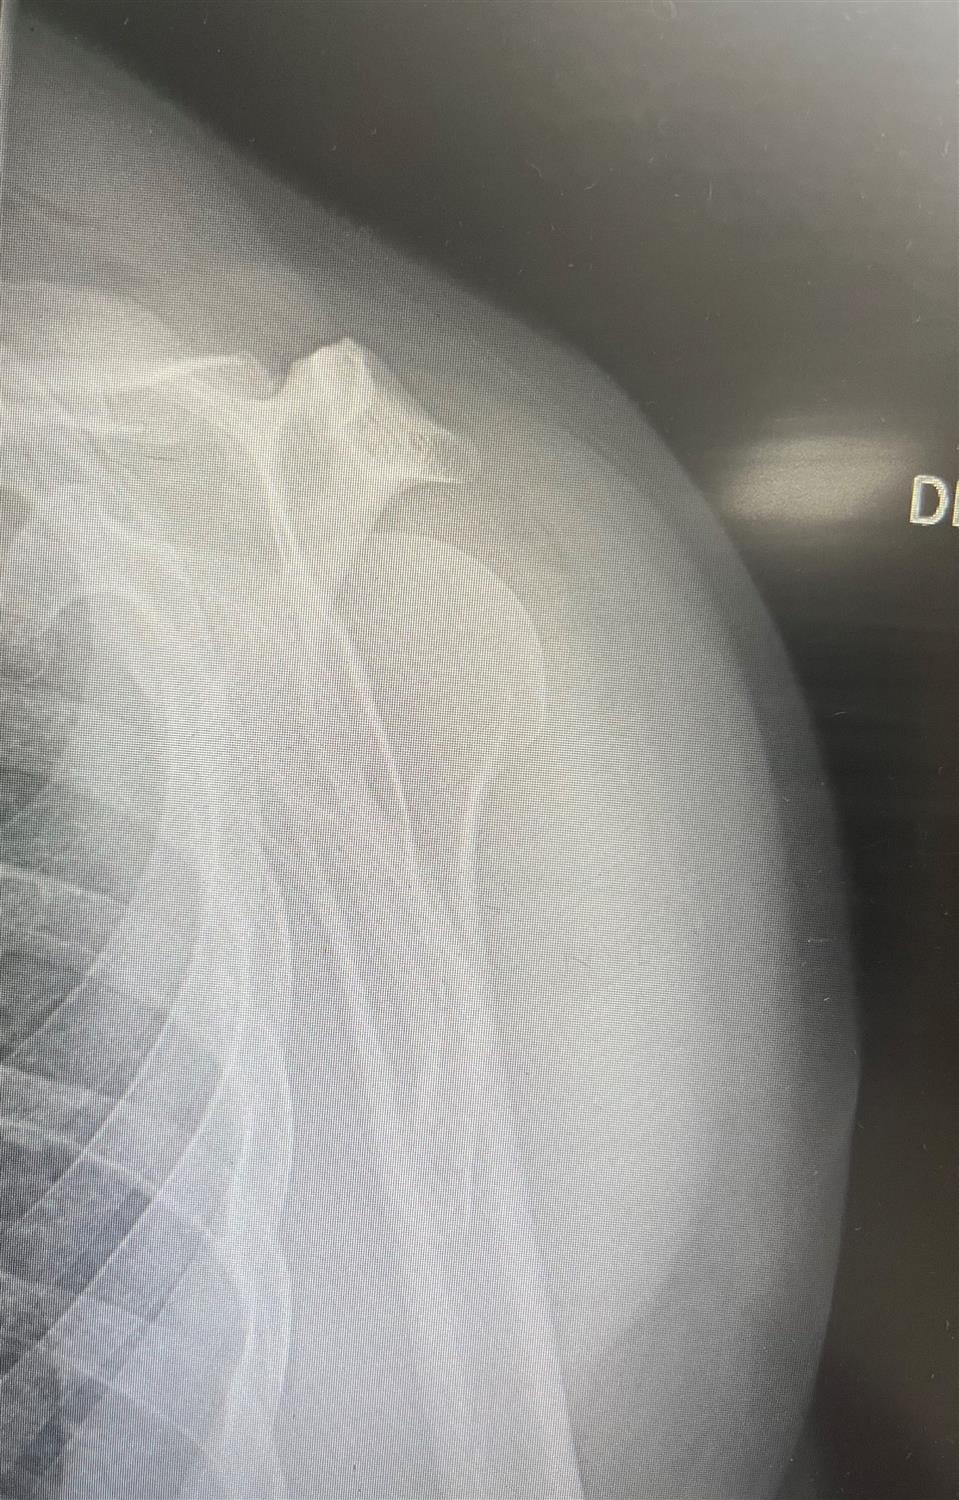

• We prospectively captured all traumatic shoulder instability events at the United States Military Academy between September 1, 2004, and May 31, 2005. Throughout this period, all new traumatic shoulder instability events were evaluated with physical examination, plain radiographs, and magnetic resonance imaging. Instability events were classified according to direction, chronicity, and type (subluxation or dislocation). Subject demographics, mechanism of injury, and sport were evaluated.